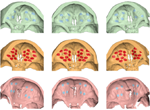

Three-Dimensional Analysis of Posterior Mandibular Displacement in Rats. Lyros I, Ferdianakis E, Halazonetis D, Lykogeorgos T, Alexiou A, Alexiou K-E, Georgaki M, Vardas E, Yfanti Z, Tsolakis AI. Vet Sci 2022;9,144. doi: 10.3390/vetsci9030144. PMID: 35324872.